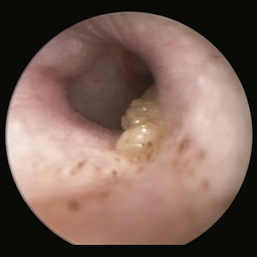

image

Figure 20-17 Ceruminolith in the horizontal ear canal of a cat.